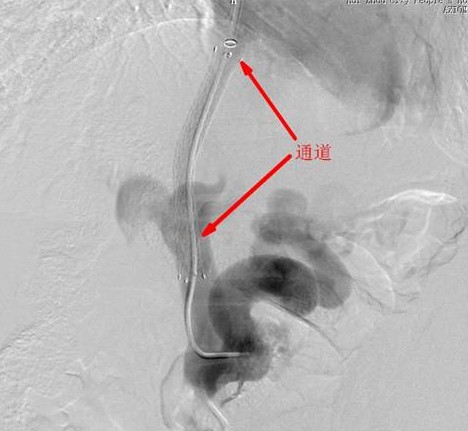

1031下午,患者被推進DSA手術(shù)室,在陳教授的指導(dǎo)下,凌主任及徐永輝醫(yī)生為患者進行局部麻醉,右側(cè)頸部靜脈穿刺成功后插入10F金屬血管鞘并導(dǎo)入8F導(dǎo)引導(dǎo)管進入肝靜脈造影,肝靜脈擴張增粗,經(jīng)導(dǎo)引導(dǎo)管內(nèi)導(dǎo)入TIPSS穿刺套裝,調(diào)整角度后對準門靜脈左支進行肝內(nèi)穿刺并回抽見靜脈血,再用高壓注射器造影證實肝靜脈——門靜脈穿刺成功(這一步是這手術(shù)的技術(shù)難點,也是關(guān)鍵,其決定著手術(shù)是否順利,以及成敗)。再導(dǎo)入導(dǎo)絲進入門靜脈,導(dǎo)絲導(dǎo)引5F-椎動脈管進入門靜脈內(nèi),造影顯示門靜脈主干明顯增粗:測量門靜脈壓力為45cm水柱(正常范圍為1324cm)。再將導(dǎo)管進入脾靜脈處高壓造影,顯示脾、食管及胃底靜脈嚴重增粗迂曲。撤出導(dǎo)管并導(dǎo)入球囊,送至肝靜脈與門靜脈間的穿刺通道,高壓擴張,撤出球囊:在通過指引導(dǎo)管植入FVM8*8帶膜支架,在DSA透視下精確定位后釋放支架安放位置至關(guān)重要),門體靜脈分流通道成功建立;重復(fù)導(dǎo)入5F導(dǎo)管高壓注射器造影證實分流通道通暢,并測定門靜脈壓力為28cm水柱,壓力明顯下降。胃左靜脈造影顯示胃左靜脈及胃底食管靜脈明顯呈臘腸樣重度擴張,最大直徑的鋼圈無法栓塞,經(jīng)導(dǎo)管注射10ML甘油酸鈉泡沫硬化劑,再次造影證實胃左靜脈血流明顯減慢。撤管把鞘按壓包扎穿刺部位后,歷經(jīng)兩個多小時的手術(shù)順利完成,患者安全返回病房。

TIPSS術(shù)簡單的說就是在肝靜脈及門靜脈之間建立一個人工分流通道,相當(dāng)于在肝內(nèi)人工開鑿了一道導(dǎo)流泄洪渠,使淤滯高壓的門靜脈的血液得到有效的分流,降低門靜脈壓力,防止再次發(fā)生消化道大出血。由于其手術(shù)難度大、風(fēng)險高、技術(shù)精度強,是公認代表外周介入治療最高水平的標志性手術(shù),目前國內(nèi)能開展此手術(shù)的醫(yī)院不是很多,此手術(shù)成功完成標志著我院外周介入達到了較高的水平。